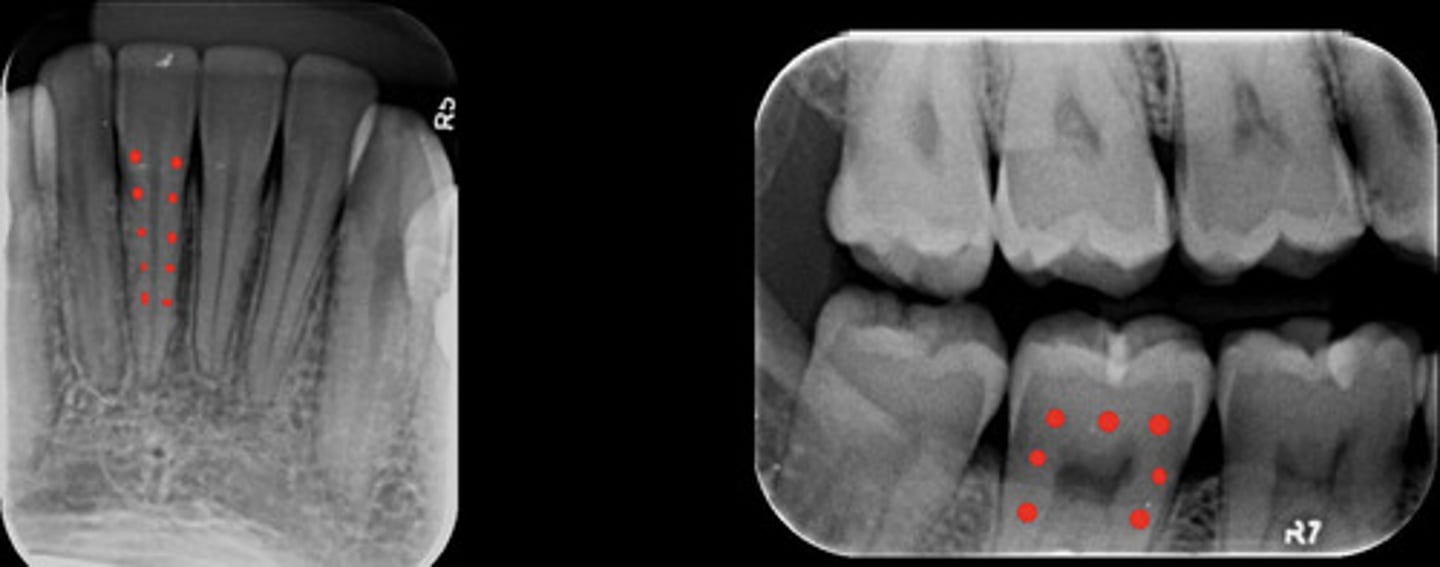

Dentin

What are the red dots representing?

Dental papilla space

Dental follicle space